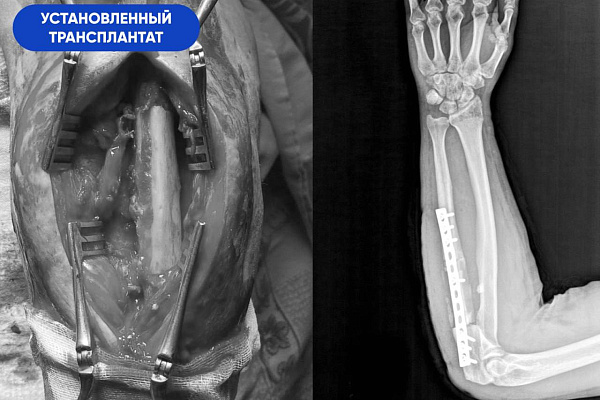

-После удаления временного имплантата мы пересадили в предплечье донорскую часть. Необходимые 8 сантиметров взяли из малоберцовой кости* и зафиксировали аутотрансплантат специальной накостной пластиной. Таким образом, весь запланированный объём хирургической работы был выполнен. Последняя операция прошла штатно. Но нужно понимать, что приживление костного блока – это сложный и длительный процесс, который сопровождается угрозой отторжения. Со своей стороны мы сделали всё от нас зависящее, чтобы этот период прошёл благополучно. Все управляемые риски нами учтены и сведены к минимуму, - отмечает Сергей Глиняный.

*Голень состоит из двух костей – опорной большеберцовой и не опорной малоберцовой. Забор трансплантата из малоберцовой кости не повлияет на функцию ноги и качество жизни пациента.